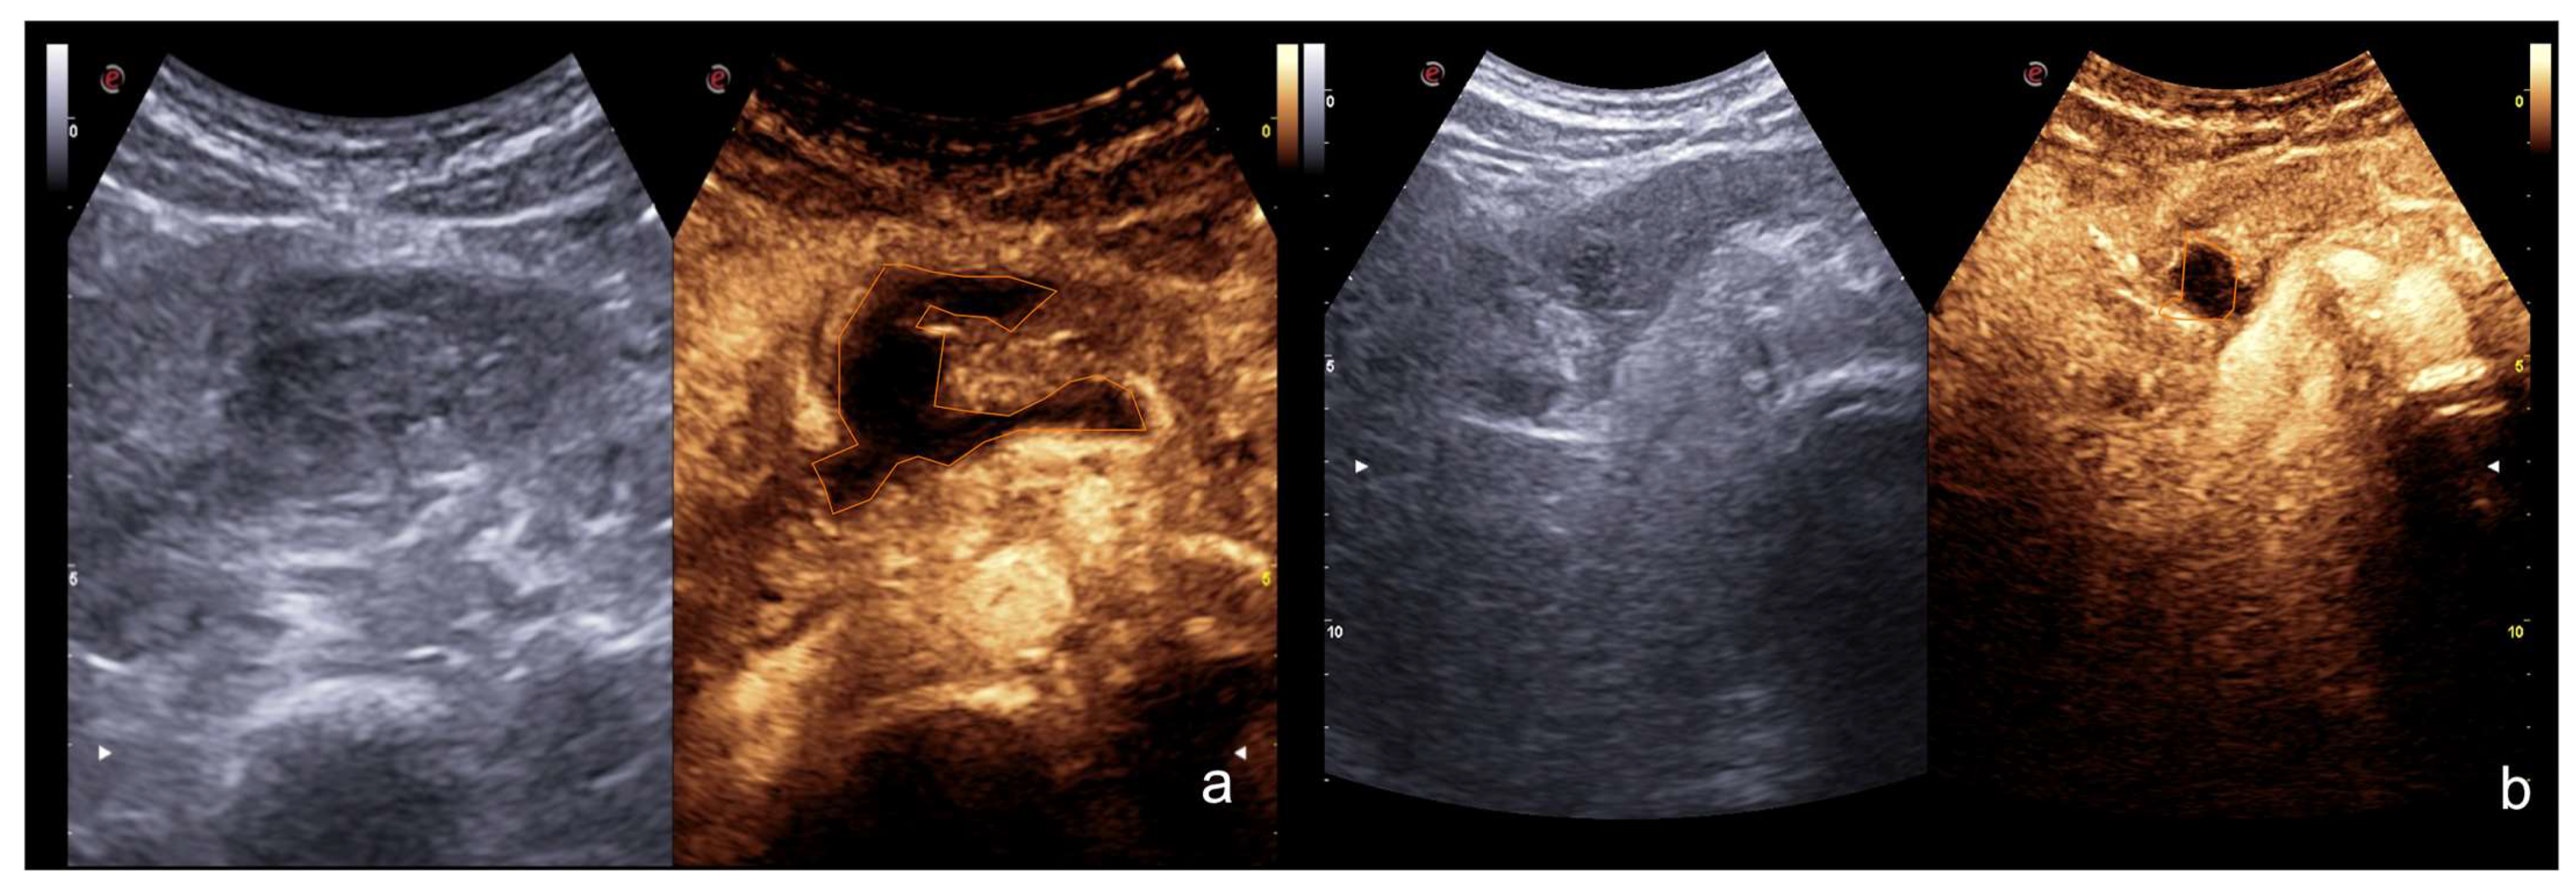

Figure 12.

Example of CEUS imaging of low grade (first column) and high grade (second column) injuries in the liver (a) and spleen (b) after moderate energy blunt trauma. Orange lines indicate parenchymal lacerations/haematomas.